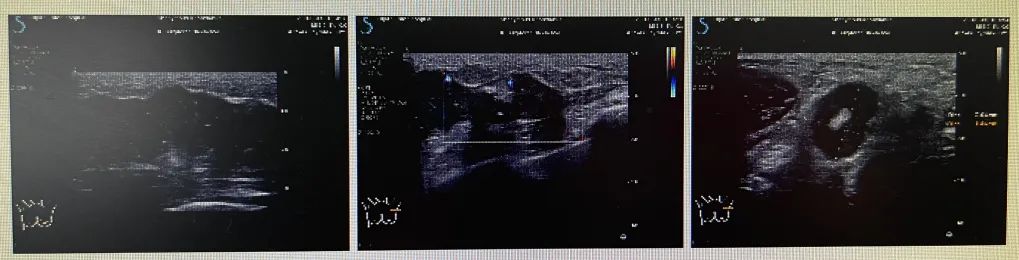

钼靶及MRI的疗效评估(如下)

疗效评估:PR